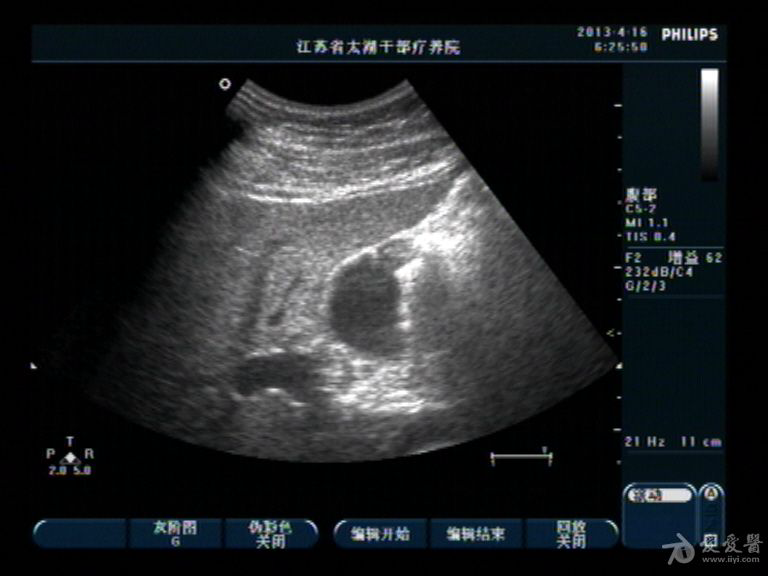

胆囊底部稍低回声区,胆泥沉积?胆囊癌不像吧?,请分析

男性,40,无右上腹痛